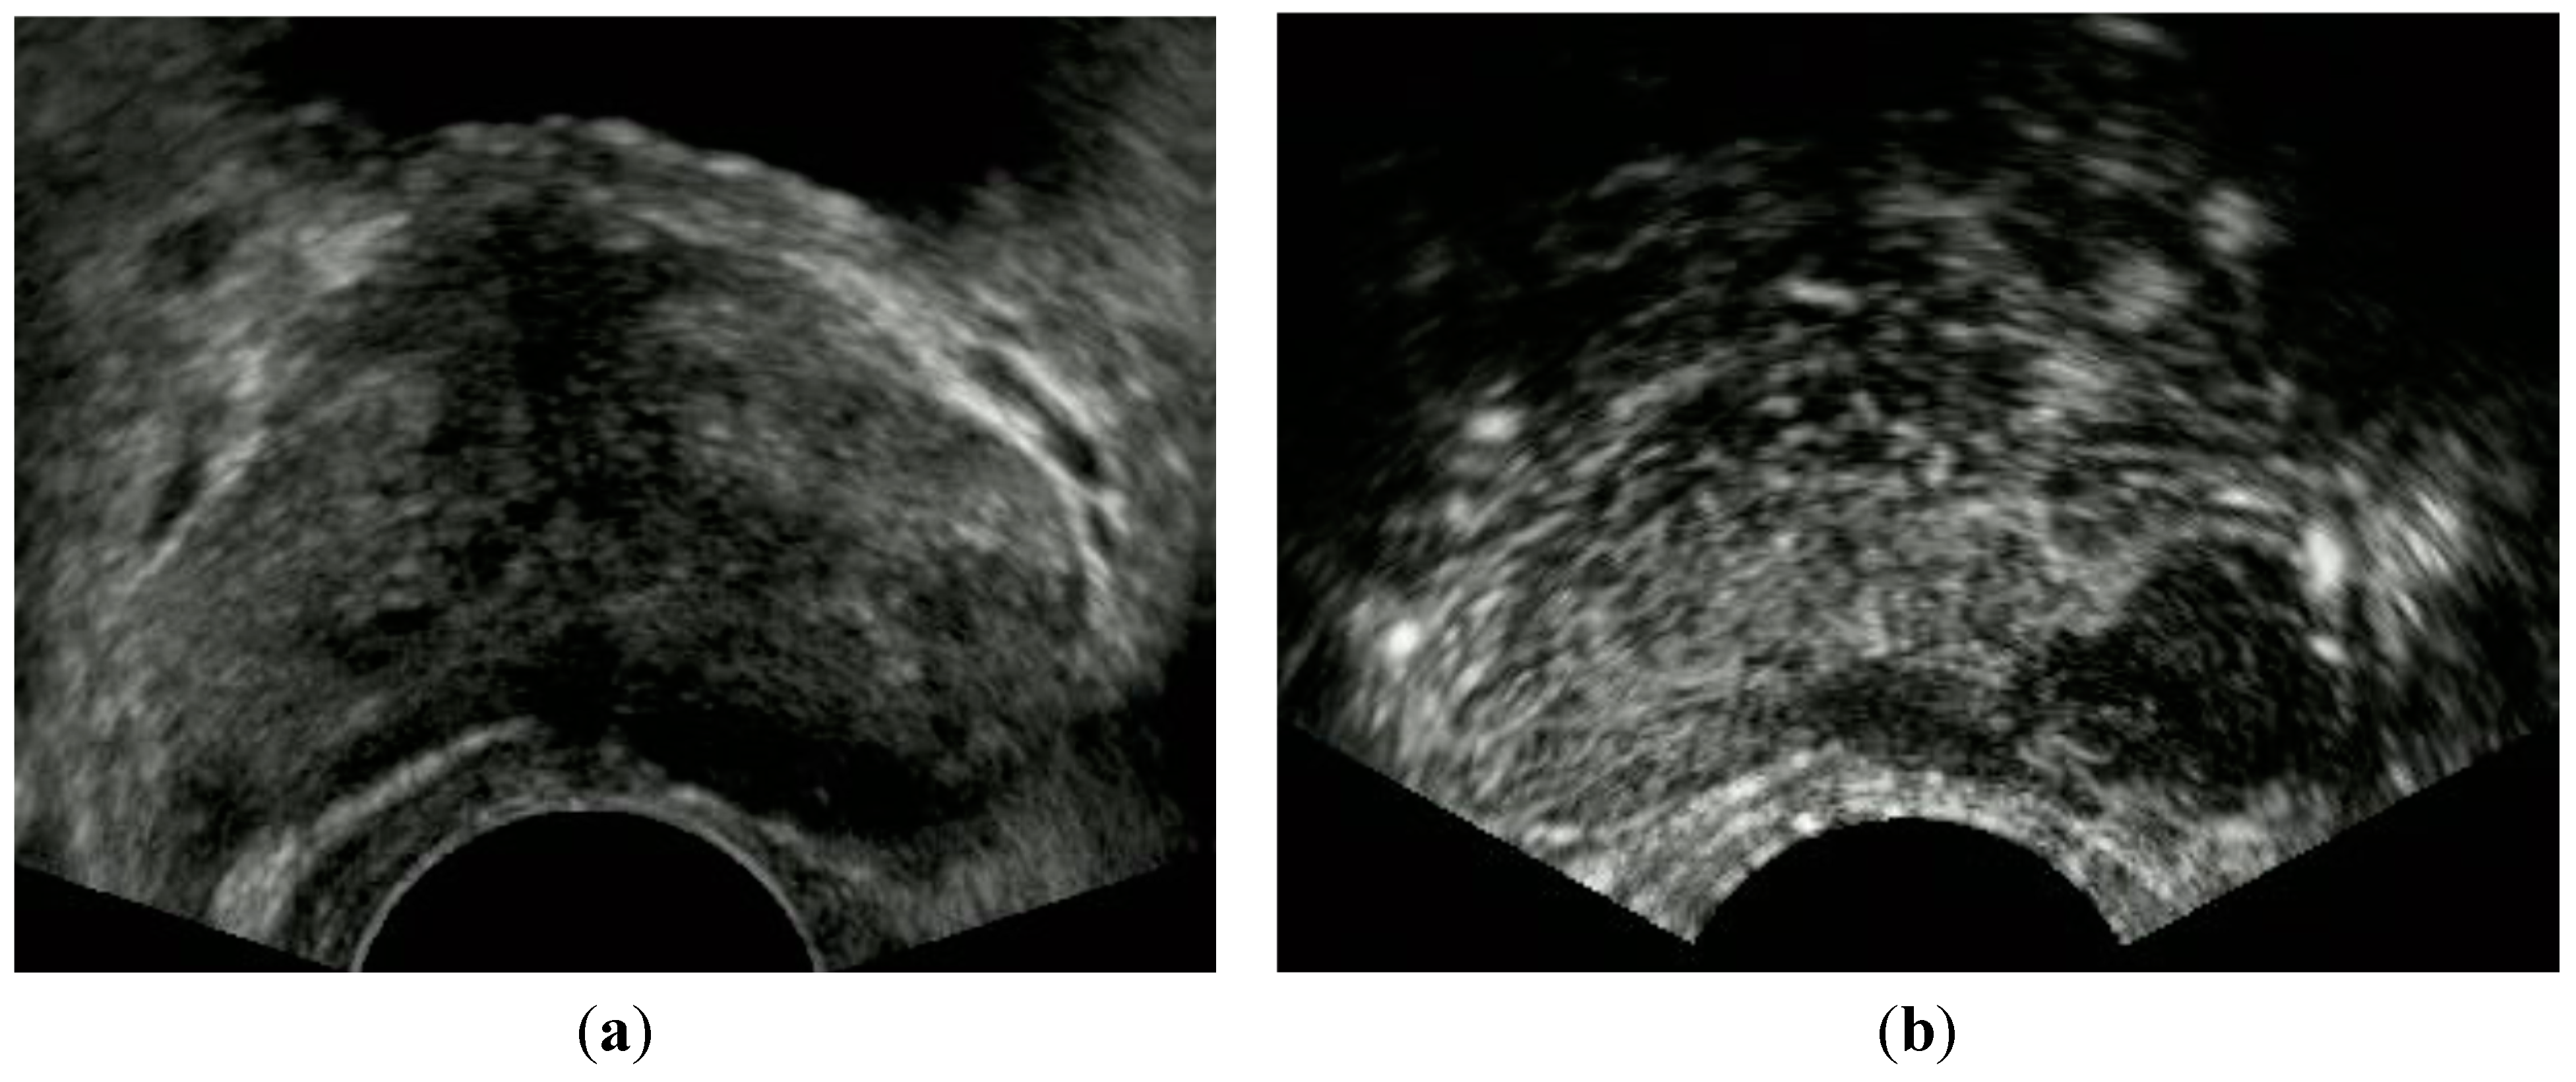

- Sano, F.; Terao, H.; Kawahara, T.; Miyoshi, Y.; Sasaki, T.; Noguchi, K.; Kubota, Y.; Uemura, H. Contrast-enhanced ultrasonography of the prostate: Various imaging findings that indicate prostate cancer. BJU Int. 2011, 107, 1404–1410. [Google Scholar] [CrossRef] [PubMed]